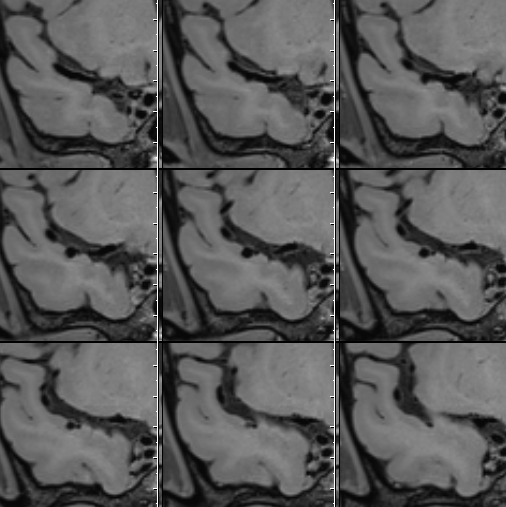

术前影像

HRMRI

左侧脑室旁亚急性期-慢性期脑梗死

右侧大脑中动脉瘤,右侧椎动脉V2-V3粗细不均伴局部扩张

右侧大脑中动脉瘤,瘤壁强化

右侧椎动脉局部梭形扩张,管壁增厚